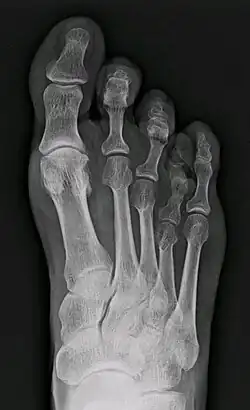

X-ray of congenital brachymetatarsia involving fourth metatarsal bone

It most frequently involves the fourth metatarsal. If it involves the first metatarsal, the condition is known as Morton's syndrome. Treatment is via a number of differing surgical procedures.[3]